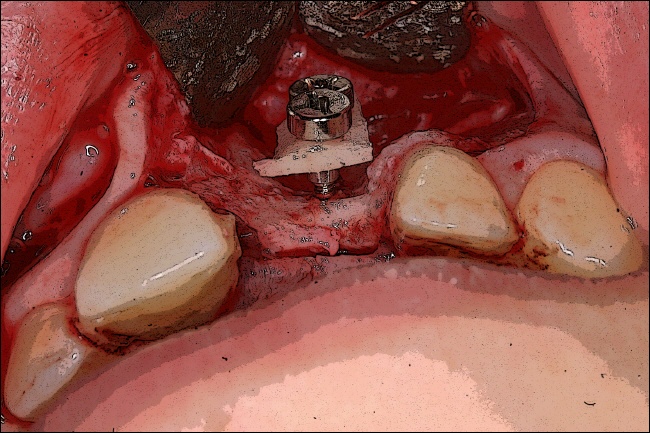

Ist der Kieferknochen in der Breite nicht ausreichend stark, so dass das Implantat nicht ringsherum von Knochen bedeckt ist, wird Knochen auf die entsprechenden Bereiche aufgelagert. Je nach individuellem Fall, wird der Knochen mit partikulärer Masse, also zerkleinerter Knochenmasse, oder aber als solider Block aufgebracht.

Mitunter muss der Knochen auch durch eine so genannte Membran (Schutzfolie) stabilisiert werden, damit er an der entsprechenden Stelle einwachsen kann. Knochenblöcke werden mit kleinen Schrauben am Restknochen lagestabil verankert. Nach der Einheilung (4-5 Monate) werden die Schrauben wieder entfernt.